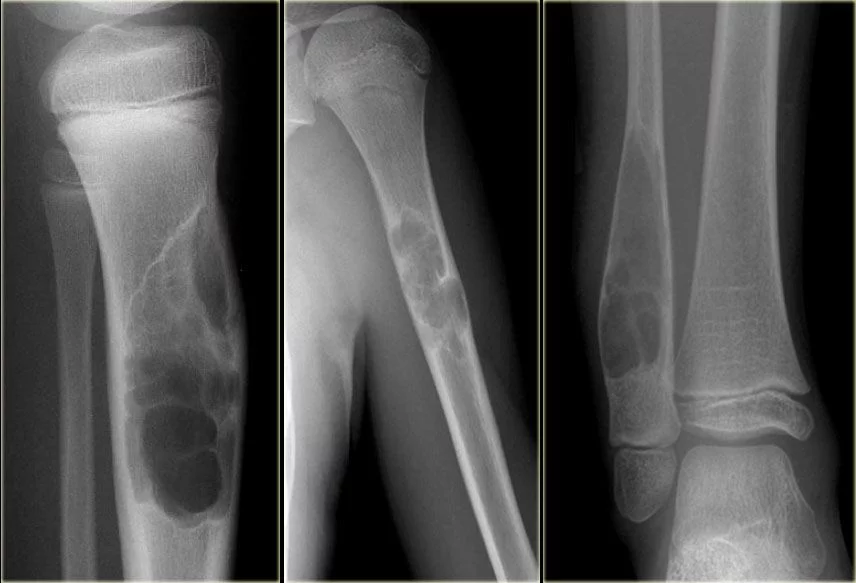

- Radyolojik görüntüleme: Röntgen, MR ve CT taramaları, kemikteki anormallikleri ortaya çıkarır.